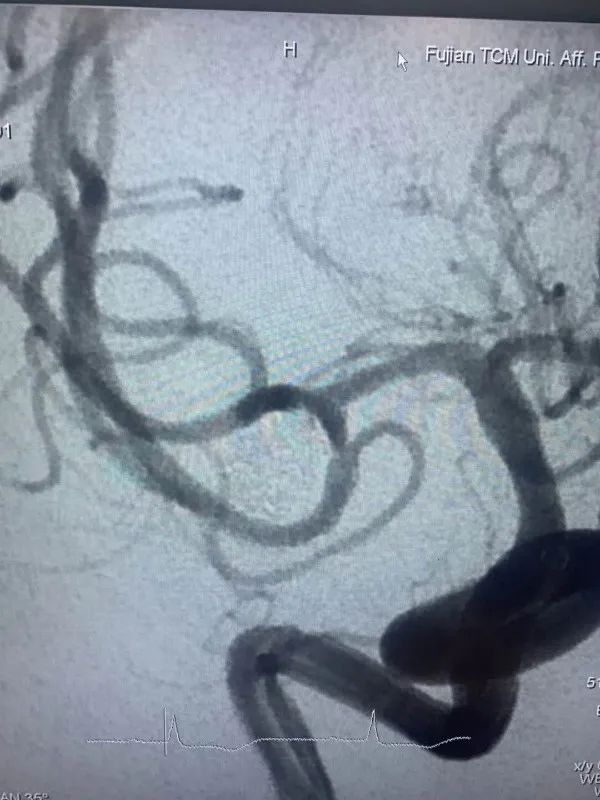

近日,省人民醫(yī)院神經(jīng)外科為一位高齡動脈瘤患者施行了介入治療,成功栓塞了破裂的大腦中動脈瘤?;颊咭蛲话l(fā)暈厥后頭痛不適入院,急診行顱腦CT檢查提示蛛網(wǎng)膜下腔出血,行顱腦CTA檢查后證實患者存在右側(cè)大腦中動脈瘤?;颊吒啐g,既往基礎(chǔ)病多,高血壓病、糖尿病、冠心病、雙側(cè)頸動脈硬化、雙側(cè)腹股溝疝術(shù)后等,手術(shù)風(fēng)險較大,經(jīng)家屬簽字同意后,當(dāng)日急診全麻下行“右側(cè)大腦中動脈瘤介入栓塞術(shù)”,術(shù)中見血管迂曲明顯,導(dǎo)管到位艱難,經(jīng)過努力,手術(shù)順利結(jié)束。術(shù)后予多次腰椎穿刺術(shù)釋放血性腦脊液,患者頭痛頭暈癥狀漸緩解?;颊咦≡褐委?/span>10天后順利康復(fù)出院,未留后遺癥。

動脈瘤主要有兩種治療方式:開顱手術(shù)和介入栓塞。兩種方法比較,介入栓塞手術(shù)時間短、康復(fù)快、不需開顱、可同時治療多個動脈瘤,適合高齡、分級高的患者,其中血管內(nèi)彈簧圈栓塞術(shù)是顱內(nèi)動脈瘤最常見的一種介入治療方式,隨著介入新材料、技術(shù)的不斷進(jìn)步,介入栓塞的優(yōu)勢日漸明顯。